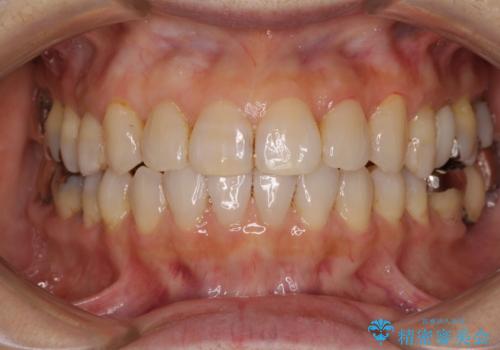

- 上の前歯の隙間を気にして来院された患者様です。

インビザラインの自己管理は自信がないとのことで、ワイヤー矯正により隙間を閉じていくこととしました。

下の前歯が上の前歯を突き上げるように咬合するため、咬み合わせの位置を改善しながら隙間を閉じていきました。

元々の歯並びが悪くなかったため、9ヶ月で綺麗に仕上がりました。

すきっ歯は後戻りを起こしやすいため、上下ともに歯の裏側を細いワイヤーで固定した上で、リテーナーのマウスピースを装着していただいています。